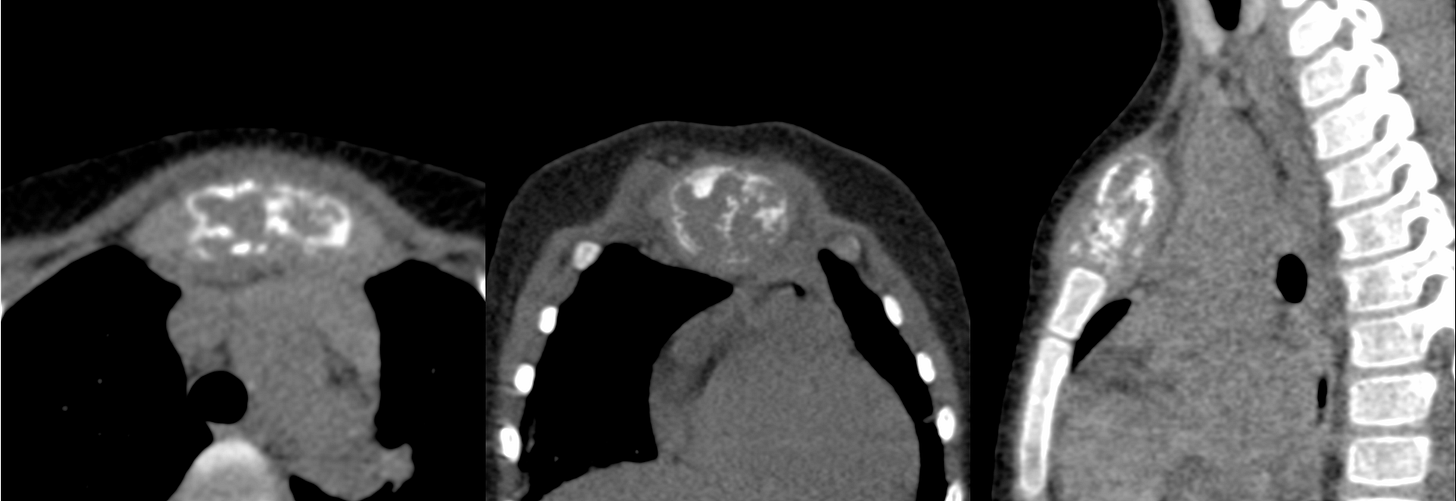

MRI showed an expansile osteolytic lesion in the manubrium sternum.

There were also enlarged left supraclavicular and mediastinal nodes.

The patient was referred for a CT guided biopsy. On CT, the lesion had a “bone-in-bone” appearance.